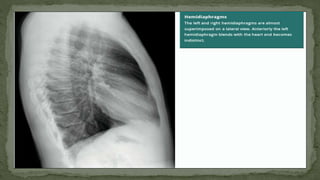

6. HEMIDIAPHRAGM